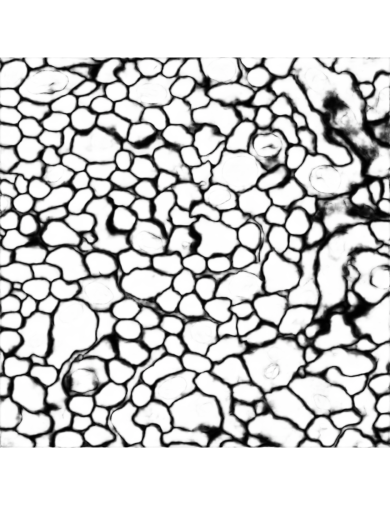

We use the dataset from the open challenge on Circuit Reconstruction from Electron Microscopy Images (CREMI)111https://cremi.org/ to evaluate the proposed invariant CNNs. The CREMI dataset consists of brain electron microscopy images (EM), and the ultimate goal is to reconstruct neurons at the micro-scale level. A critical first step in neuron reconstruction is to segment the EM images. The main objective of neuron segmentation is to distinguish different neuron objects in the electron microscopy images. A common way for segmenting EM images is to predict the neuronal boundaries in the images [15]. For each pixel in the dense prediction output, there will be two labels with corresponding probabilities. Class 1 pixels correspond to boundaries in the image, and class 0 pixels correspond to all other structures. This task has an additional problem of imbalanced samples since there are far less boundary pixels in the image than non-boundary pixels. Thus, the commonly-used accuracy metric may not correctly reflect the performance of dense prediction models. In this situation, the ROC curve is used to evaluate models involved in this work, which could avoid the influence of imbalanced labels.

Refer to captionRefer to captionRefer to captionRefer to captionInput imageBaseline without data augmentationBaseline with data augmentationNew model without data augmentationRefer to captionRefer to captionRefer to captionRefer to captionInput imageBaseline without data augmentationBaseline with data augmentationNew model without data augmentation\begin{array}[]{cccc}\includegraphics[width=203.80193pt]{FIG/outputsub1.pdf}&\includegraphics[width=203.80193pt]{FIG/outputsub2.pdf}&\includegraphics[width=203.80193pt]{FIG/outputsub3.pdf}&\includegraphics[width=203.80193pt]{FIG/outputsub4.pdf}\\ \mbox{Input image}&\mbox{Baseline without data augmentation}&\mbox{Baseline with data augmentation}&\mbox{New model without data augmentation}\end{array}

Figure 8: Comparison of the results generated by the three models. The inputs are brain electron microscopy images, and the outputs are boundaries of neurons.

IV-E Analysis of Results

The dense prediction outputs of three models are given in Figure 8. Figure 7 shows the training loss of the three models at different iterations. The training loss of the baseline model without data augmentation is the highest among the three models. The new model without data augmentation even has the lowest training loss along the whole training iterations. This means the property of rotation and flip invariance in the new model help improve the training, since it could deal with features with arbitrary rotation and flip transformations. The baseline model without data augmentation does not have this invariance capability. The baseline model with data augmentation may be trained to learn this property but with much more iterations. From these results, it is clear that the baseline model with data augmentation has larger loss than the new model until after 35,000 iterations. But the loss of the baseline model without data augmentation is always higher than that of the new model. The gap between the loss curves of the baseline model without data augmentation and the new model even increases as iteration number increases.

Table I shows the model evaluation results using AUC values. Since the prediction output labels are imbalance, AUC values would be more meaningful in the evaluation. The AUC values of the new model and baseline model with data augmentation are similar and higher than that of the baseline model without data augmentation. This shows that the new model has very similar performance compared to the baseline model with data augmentation. This also demonstrates that data augmentation usually leads to improved performance, a results that is consistent with prior observations [16]. Figure 6 gives the ROC curves of three models.